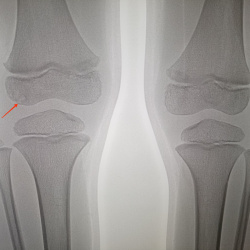

6 лет, жалоб на боль в коленном суставе не предъявляет, травм не было, что за участки просветления в области эпифиза?

17.04.2024 - 09:41